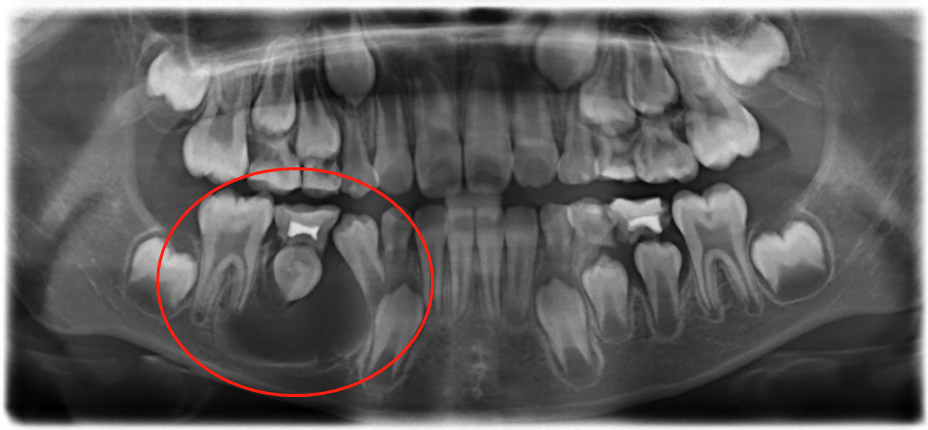

在X光片显示下,鹏鹏右下颌骨有大面积囊性阴影,而且松动的乳磨牙和未萌出的恒牙已经出现牙根外吸收的现象,如不给予治疗,囊肿有可能吸收掉整颗恒牙和部分颌骨骨质。

经过与家长沟通,王静静医生为鹏鹏定制了治疗方案,采取“开窗减压术”,即在鹏鹏的颌骨上局部打开骨质及囊壁,引流出囊液,并制作阻塞器保持引流口通畅,使囊腔内外压力保持平衡,在颌骨的功能活动状态下,囊肿外周骨能得到新生,囊腔逐渐缩小,使外形得以恢复。

在深圳远东医院集团口腔学科带头人黄盛兴教授的指导下,王静静医生为鹏鹏实施了“开窗减压术”,开窗去骨打开囊肿,抽取囊液,并用无菌性生理盐水反复冲洗后进行缝合。囊液取出后,鹏鹏的右下颌骨露出颊侧5mm*5mm的囊腔,然后佩戴上阻塞器,维持创口持续开放,便于囊液引流和冲洗,还能防止邻牙移位,起到间隙保持的作用。

在术后第十天,鹏鹏到院复查,囊腔成愈合状态,恢复良好,继续佩戴阻塞器,保持开窗减压;术后四个月,鹏鹏进行X光片复查,显示囊肿界限开始模糊,囊腔面积缩小,囊肿包裹的恒牙有萌出迹象;术后十个月,囊肿已经消失,囊腔愈合,恒牙萌出。但是王静静医生表示,由于鹏鹏的恒牙没有全部萌出,牙齿的后续发育情况会怎样,无法预知,需持续追踪,同时希望家长定期带鹏鹏进行检查,监测牙齿和颌面部的发育情况。